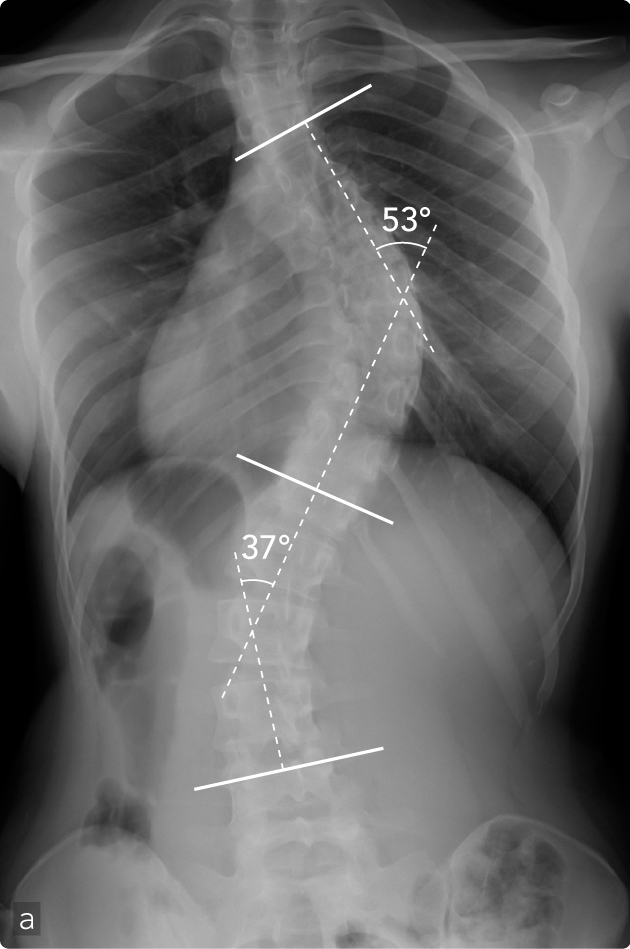

Femmina, 15 anni, scoliosi idiopatica. All'esame ispettivo si apprezza asimmetria dei fianchi, lo sbilanciamento delle spalle rispetto al bacino, la presenza del gibbo dorsale destro alla flessione anteriore del tronco (a). La radiografia mostra scoliosi toracica destra con compenso non strutturato lombare. Operata di artrodesi breve posteriore strumentata (b) con buon risultato estetico e funzionale. Si apprezza al controllo evolutivo buon bilanciamento della colonna vertebrale. Riduzione della deformità toracica da 53° a 20° secondo Cobb e della lombare da 37° a 18° secondo Cobb.